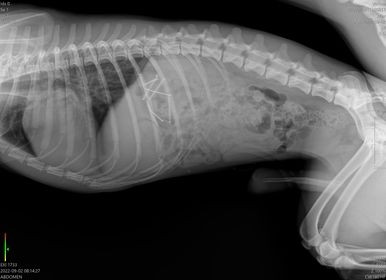

Na RTG snímke vidno špendlíky v tráviacej súsatve psa.

To, čo prežila následne, neželá žiadnemu psičkárovi. „Museli sme okamžite konať. Dohodli RTG vyšetrenie oboch psov vo veterinárnej nemocnici, kde sa ukázalo, že Max má v žalúdku osem špendlíkov a Barry jeden. Oba psy museli podstúpiť klinické vyšetrenia a operačný zákrok, gastrotómiu... Všetky špendlíky sa doktorom podarilo zo žalúdka vytiahnuť. V ten istý večer bola na RTG aj naša suseda, ktorej pes doma takisto vyvrátil špendlík, no našťastie ich v sebe už viac nemal.“